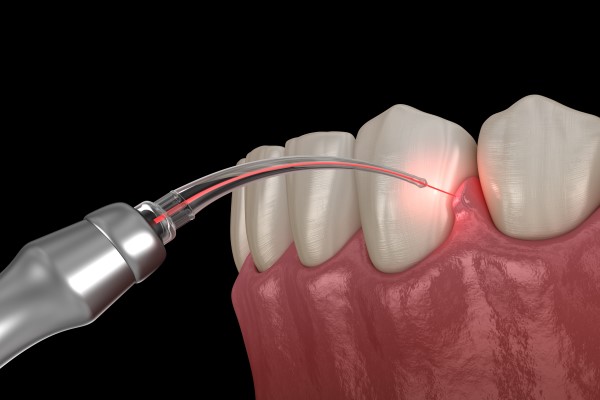

Perhaps one of the most significant advances that gentle dentistry has made is associated with treating gum disease. This condition is so common that most adults will suffer from some form of gum disease in their lifetime. The symptoms typically start with red, swollen, and bleeding gums but if left untreated, it can lead to gum recession. Receding gums are particularly dangerous because more of the tooth and roots will become exposed and open for attack by bacteria. Many people suffer bone and tooth loss as a result. Treating gum disease, therefore, is critical for preserving your teeth as you age. The traditional method of treatment involves pulling the gums away from the tooth and using metal dental tools to scrape off the bacteria, plaque and tartar that has formed on the tooth but underneath the gums. This can be uncomfortable to say the least. Laser dentistry has completely changed the procedure. We offer periodontic care, and our patients can have their gum disease treated by using lasers to break up the plaque and tartar. This will remove the irritant that is causing the gum disease in the first place. Typically, the gums will then return to good health. Since this is a non-invasive procedure, our patients start to feel better right away. Not all dentists in the Red Bluff area offer this new method of treating gum disease, making it important to visit a laser dentistry office.